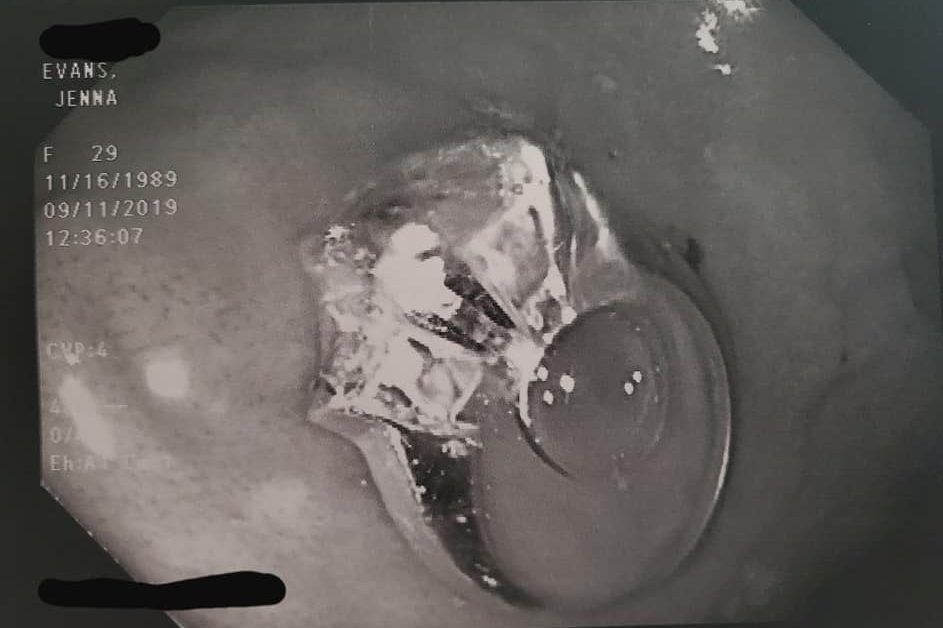

An engagement ring is shown in Jenna Evans’ stomach in this endoscopy photo. Jenna Evans/Facebook

A ring is shown in Jenna Evans’ stomach in this X-ray photo. Jenna Evans/Facebook